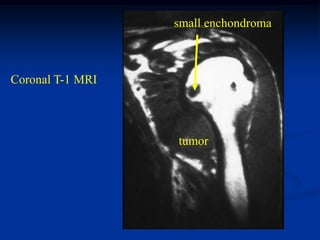

Case #587

42 year male with

combined periosteal

chondroma and

enchondroma next to

each other in femur

enchondroma

Bone scan

periosteal chondroma

Sagittal CT scan

Axial CT scan at level of enchondroma

periosteal

chondroma

CT scan

Coronal T-1 MRI

Axial T-1 MRI